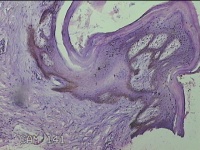

骶尾部包块

性别

男

年龄

37岁

临床诊断

骶良性肿瘤

一般病史

发现骶尾部包块10年余。

标本名称

大体所见

灰白粉红色组织3.5x1.3x1cm一块,表面带梭形皮肤3.5x1.3cm皮下见包块3x1.3cn一个,切开包块呈实性,切面灰白粉红色,质中。

图1